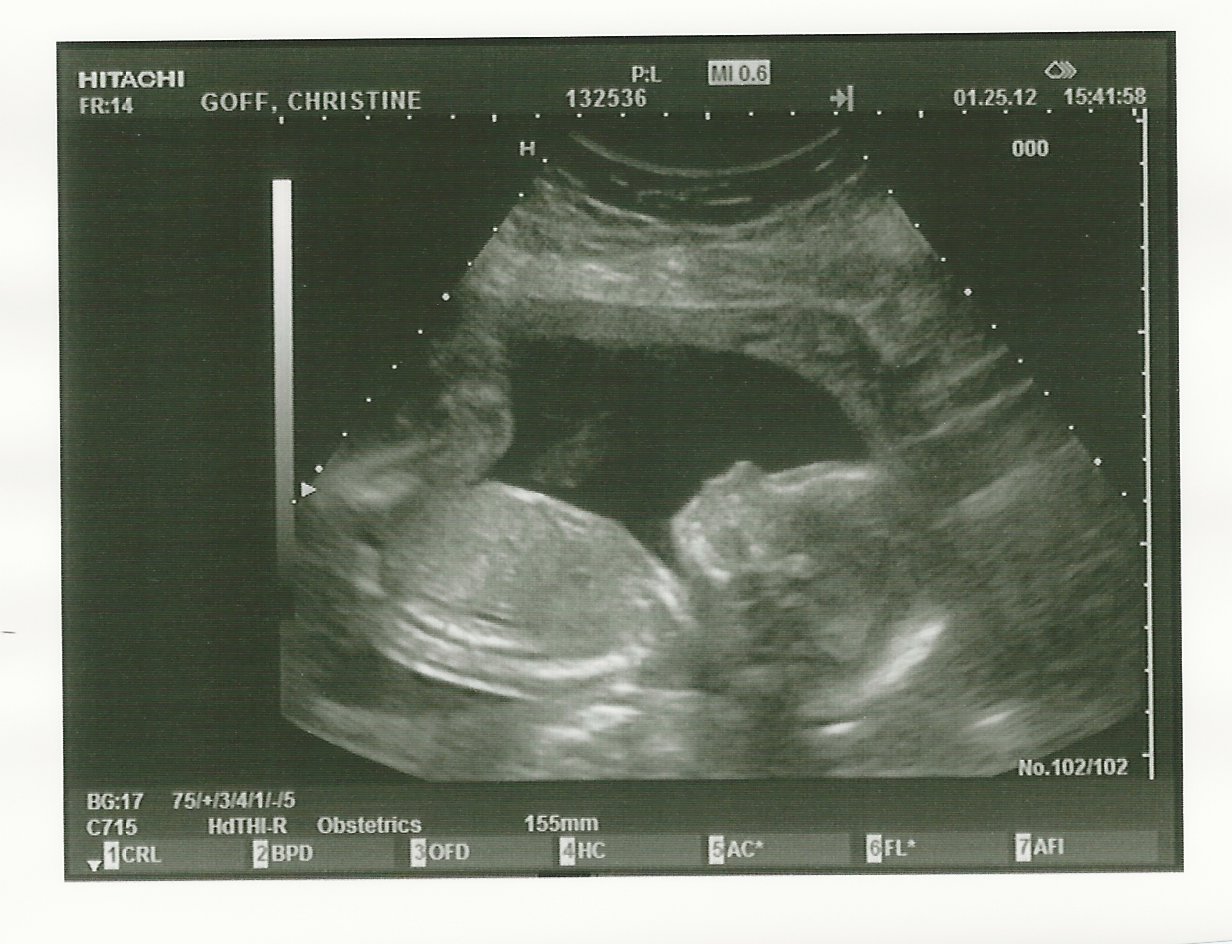

So, without further adieu, here is the latest photo of our little princess:

Isn’t she great? I thinks she has my nose.

This was my third ultrasound and it was so incredibly cool. Right away the tech pointed out that it was a girl, and Christine and Margie all cheered and were so excited. I still had to process it. There was no disappointment, I just needed the tech to go through everything first to make sure there wasn’t anything wrong before I cheered.

The tech went through all of the measurements she needed to go through and was great at explaining what everything was. To me, most of the things she was pointing out just looked like a bunch of gray and black blobs.

The coolest part was seeing the spine, the profile, and to watch the beating heart and for her to point out that everything that was supposed to be there, was there. I’m not going to lie, I had horrible dreams last night that the tech was going to point out that my child had one arm, 3 legs and an ear where one of the eyes should be. Or, a real-life picasso painting. I was very thankful that the baby was doing well.